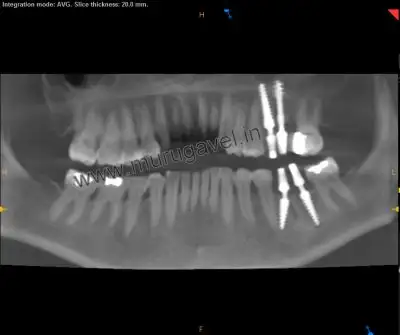

Postoperative X-Ray

It shows that teeth replacement done with dental implants engaging the basal bone.